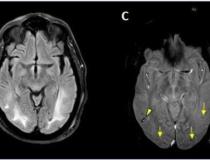

Stroke seen in a 41-year-old male patient with COVID-19 infection. Image courtesy of RSNA

-

CT showing hemorrhage in a 68-year-old male patient with COVID-19 infection. Image courtesy of RSNA